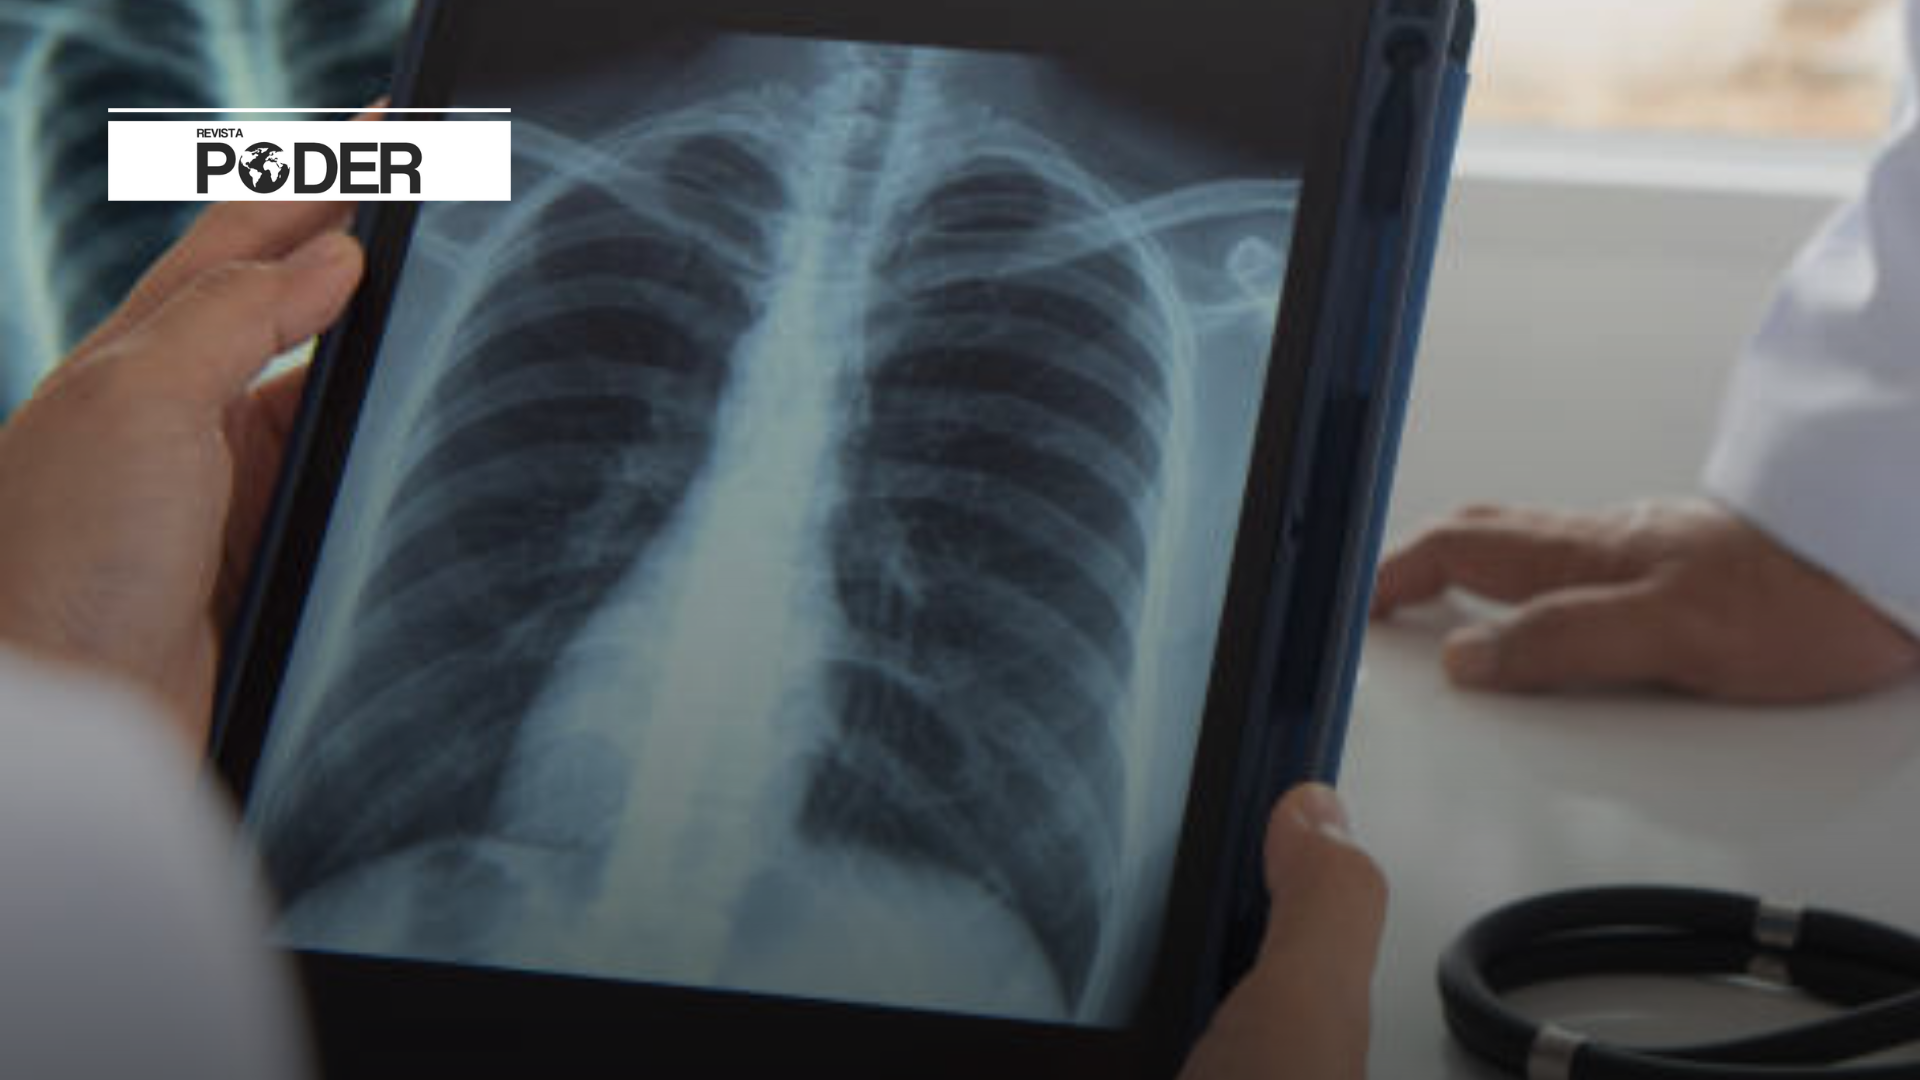

Uno de los factores que pueden haber influido en el incremento en los registros de tuberculosis es el mayor uso de radiografías de tórax durante la pandemia de COVID-19. Esta situación permitió detectar más casos que en años anteriores, revelando la persistencia del problema y la necesidad de reforzar las estrategias de atención.